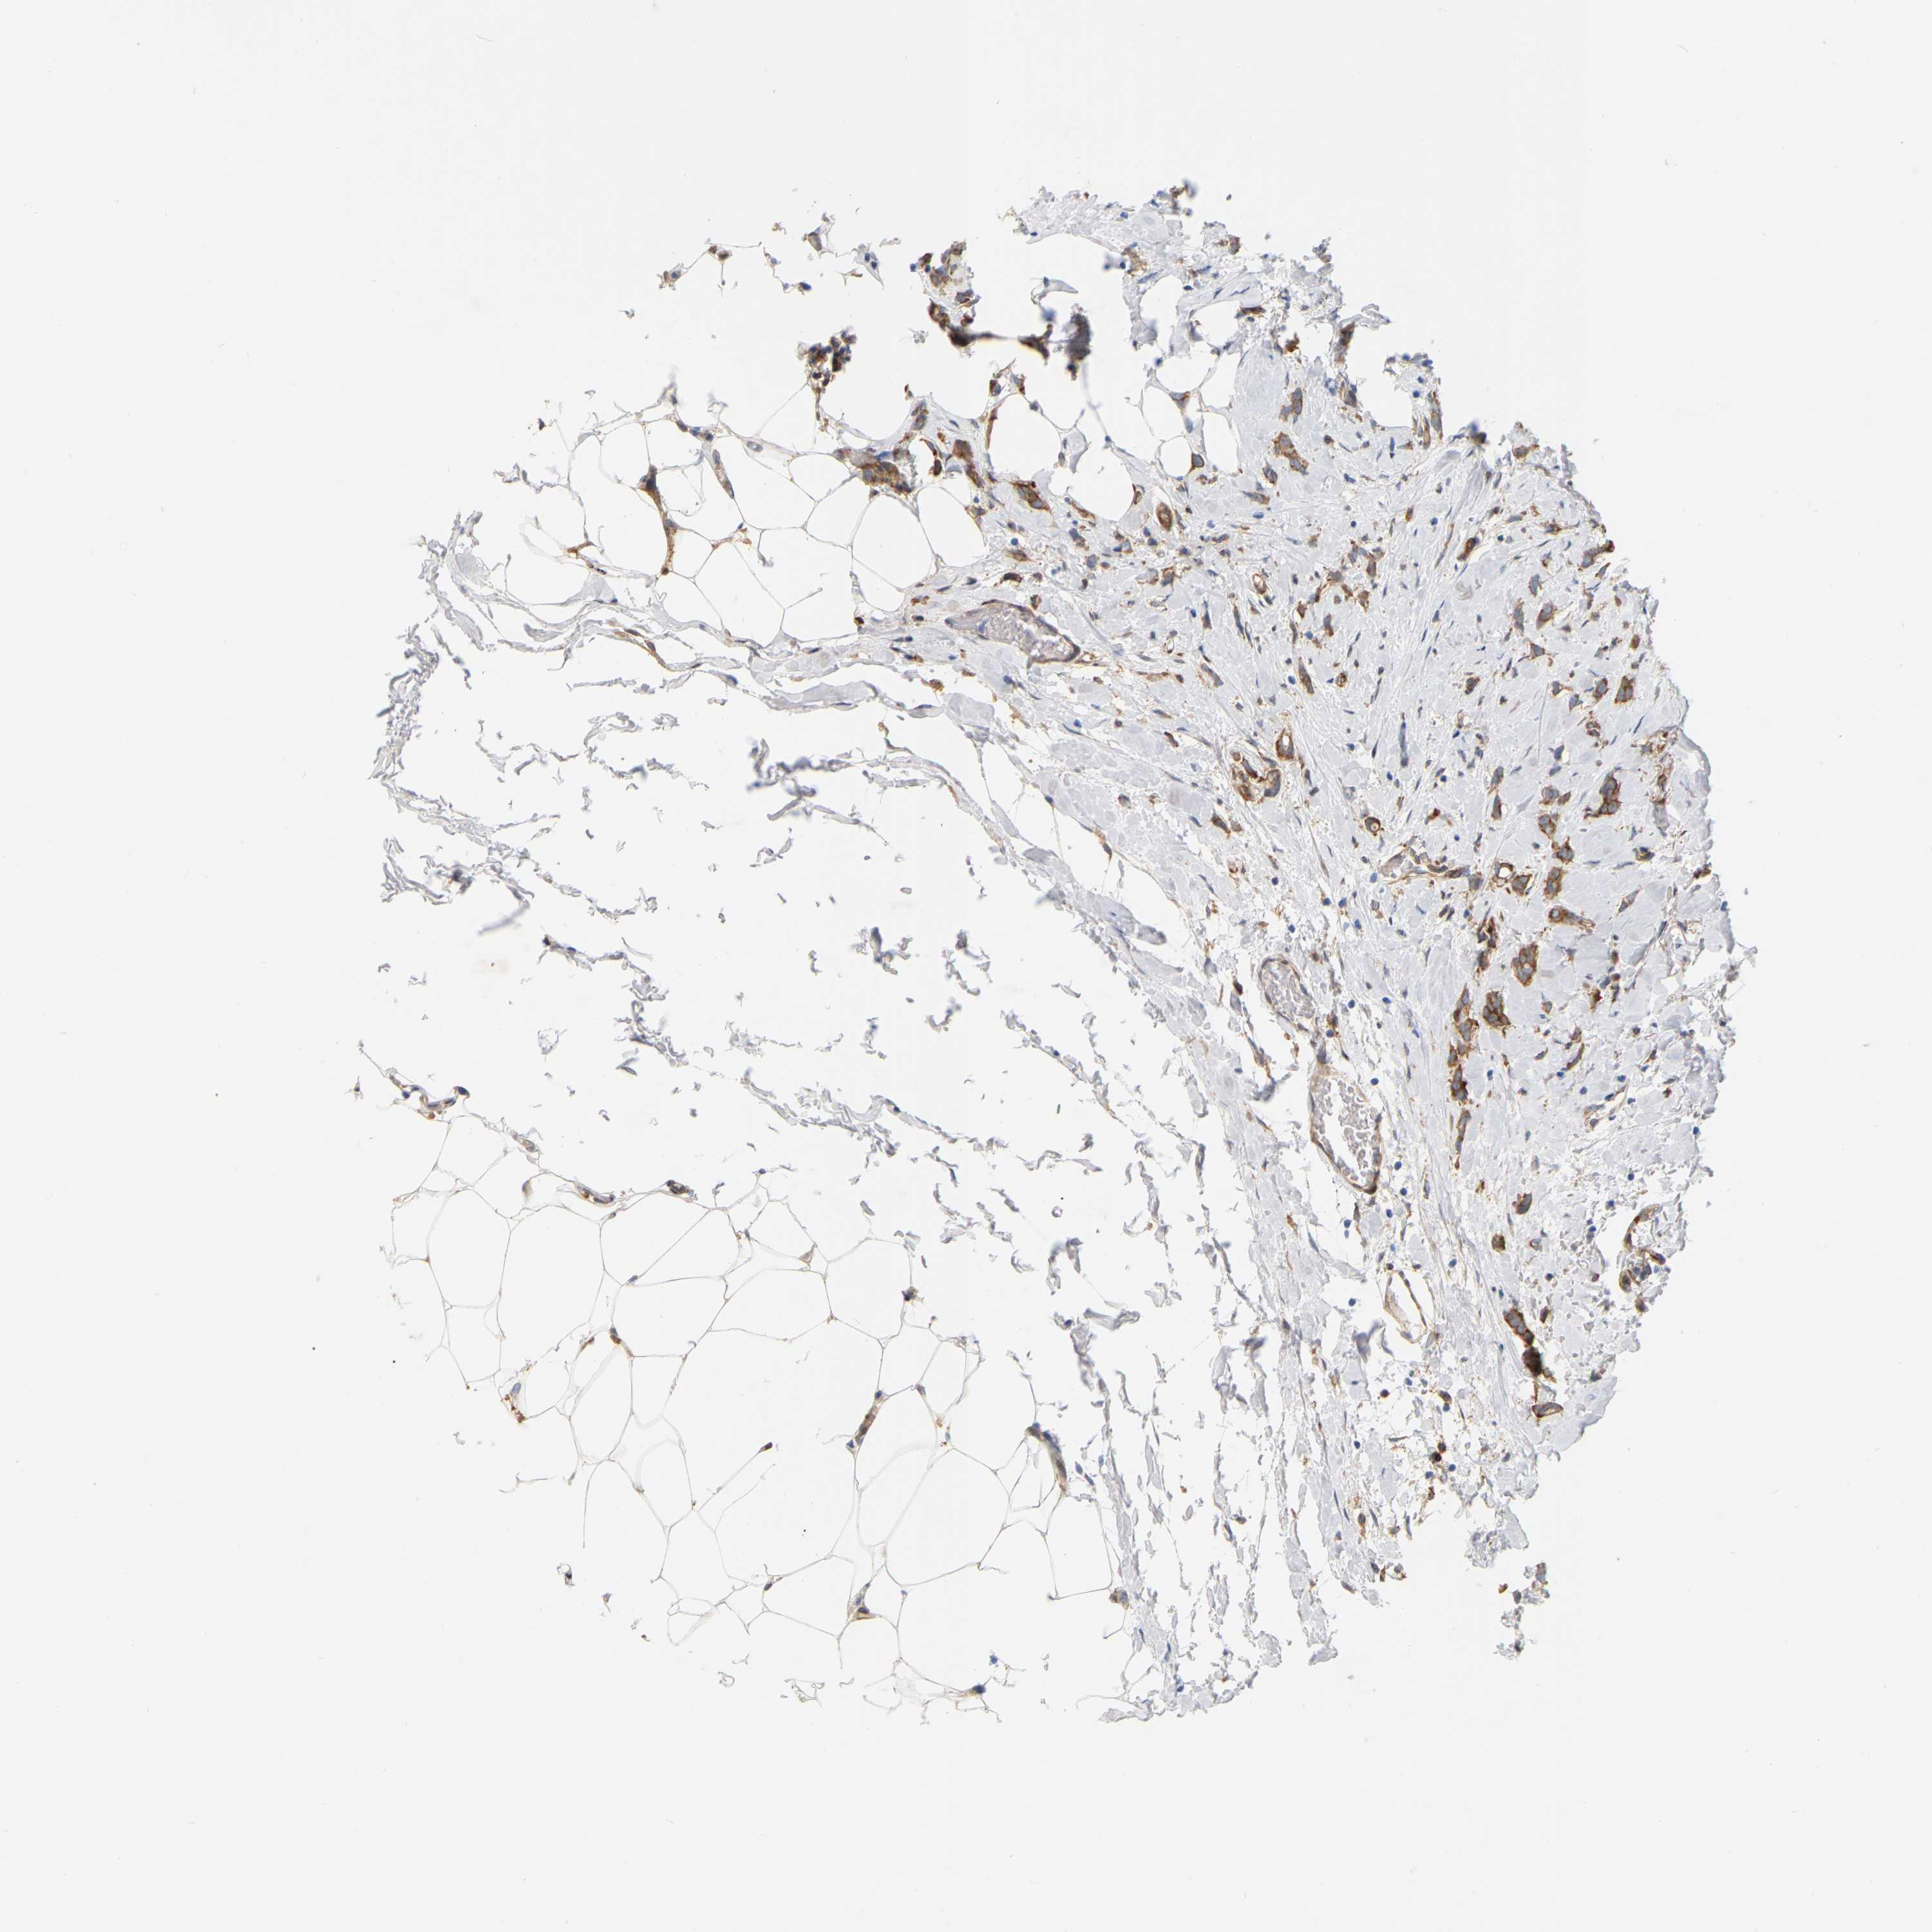

BRCA TCGA BRCA VALIDATION PROTEIN EXPRESSION

ANTIBODIES

AND

VALIDATION